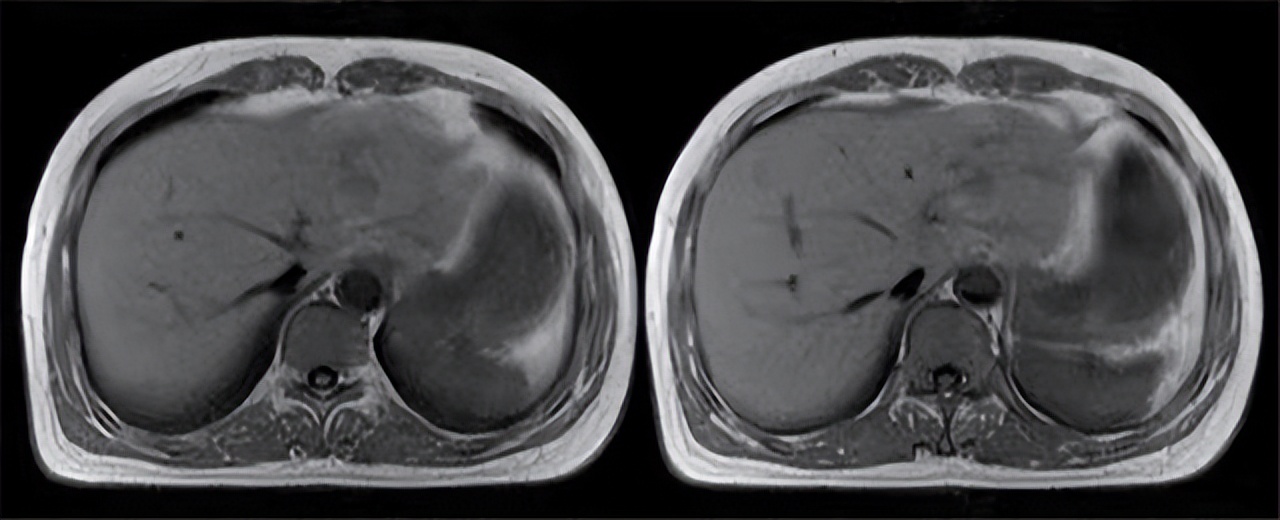

通过肝脏超声检查和CT检查并没发现肝脏异常肿块,肝脏并未发生结构性病变,早期肝脏肿瘤通过影像检查通过影像检查可能无法发现,随后为李先生检查血清肿瘤标志物,诊断肝癌的生化指标主要是甲胎蛋白(AFP),化验结果显示李先生甲胎蛋白质正常,结合影像学检查排除李先生肝癌可能性; 通过肝功能检查和血常规检查,基本确定李先生发生了肝炎,随后筛查肝炎病毒抗体,排除是病毒性肝炎,最终确诊为酒精性肝炎。

3)确诊肝癌仍需进行影像检查,肝脏影像检查是早期筛查肝癌的重要手段 。

通过肝脏影像学能够观察肝脏是否发生了病理性结构变化,肝脏CT检查能够发现肝脏组织内是否有肿块,如肝脏内部出现了病灶结合谷丙转氨酶升高,则患者可能发生了肝脏肿瘤,为了进一步确诊是否是肝脏肿瘤,可以通过肝脏穿刺活检。